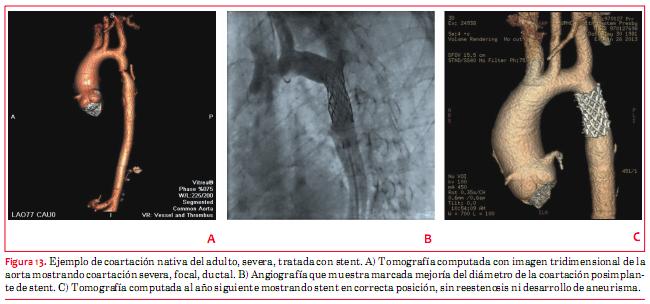

b. Coartación de aorta (CoAo)

La CoAo en el adulto puede ser nativa o residual posoperatoria. La indicación de intervención es la presencia de hipertensión arterial asociada, con un gradiente pico sistólico de por lo menos 20 mmHg (clase I)(1). También se considera indicación clase I si el gradiente es menor pero el paciente tiene extensa circulación colateral asociada a una CoAo severa en la imagen angiográfica, por resonancia o tomografía. La CoAo en el adulto, además de presentar hipertensión arterial, está asociada a enfermedad coronaria precoz, insuficiencia cardíaca y accidentes cerebrovasculares debido a aneurismas cerebrales. En el adulto se prefiere el uso de stent, dado que en general no existen las limitaciones del paciente de edad pediátrica en cuanto al tamaño de la arteria femoral, ni el problema relacionado al crecimiento. En EEUU solo se tiene acceso al CP Numed stent recubierto, el cual se encuentra en etapa de investigación (figura 12). Existen pacientes con alto riesgo de disección para quienes es esencial contar con stents recubiertos. Estos incluyen: coartaciones severas de menos de 5 mm de diámetro, pacientes de edad de más de 60 años, síndrome de Turner o Marfan, pacientes con dilatación aneurismática de la aorta. De todas maneras, no es posible predecir completamente qué paciente puede desarrollar un aneurisma o una disección, con sangrado, y necesitar el implante de un stent recubierto de emergencia, por lo que se recomienda siempre disponer de los mismos cuando se realizan este tipo de intervenciones. El éxito del procedimiento es de más de 95%, con una incidencia de complicaciones relativamente baja (1%) que incluyen disección y aneurisma(27-29). La morbilidad quirúrgica es relativamente más elevada, incluyendo derrame pleural, hemótorax, parálisis de los nervios laríngeo y frénico, así como la formación de aneurismas. Por lo tanto, para pacientes que son candidatos a la intervención percutánea, se prefiere el procedimiento percutáneo al quirúrgico. Como todo stent arterial grande, el manejo incluye el uso de antiagregantes plaquetarios por seis meses. Luego de la intervención, sea percutánea o quirúrgica, se recomiendan estudios de imagen por lo menos cada cinco años, para evaluar al área de intervención y detectar el eventual desarrollo de aneurisma aórtico (figura 13a, 13b y 13c).